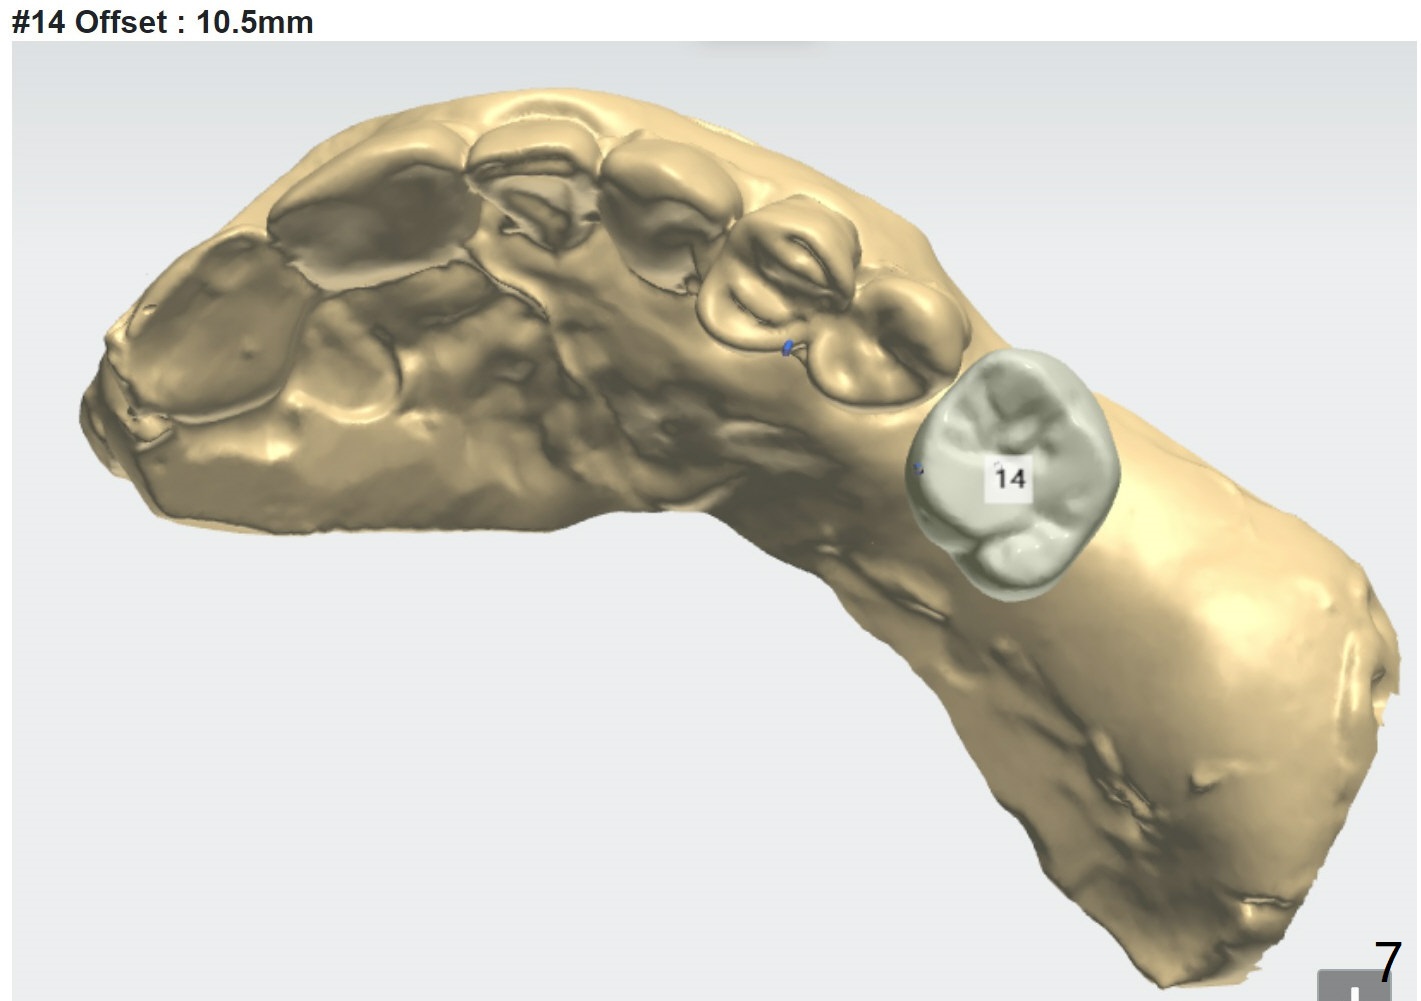

#14 Indistinct Buccal Plate

A 80-year-old man requests implants to replace his missing teeth. #14 incision for bone graft. PRFx2. Tatum 14 mm for #14 and 19, 14 or 17 mm for 20. Prepare taps.